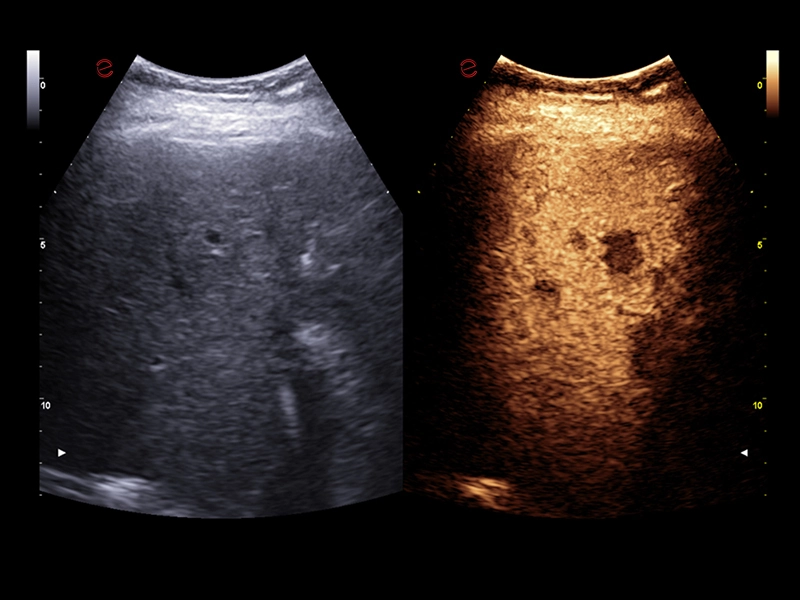

MyLab™E80 - CEUS - Liver

MyLab™E80 - CEUS - Liver